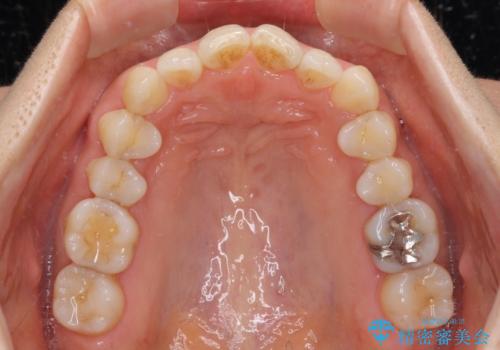

インビザライン・ライトは提供されるマウスピースの数に制限があり、通常のタイプよりもマウスピース提供期間が短くなっている一方、安価に治療を行うことができるプランです。

治療のゴールも変更できないため、軽微な歯列不正や、後戻り改善などに適しています。